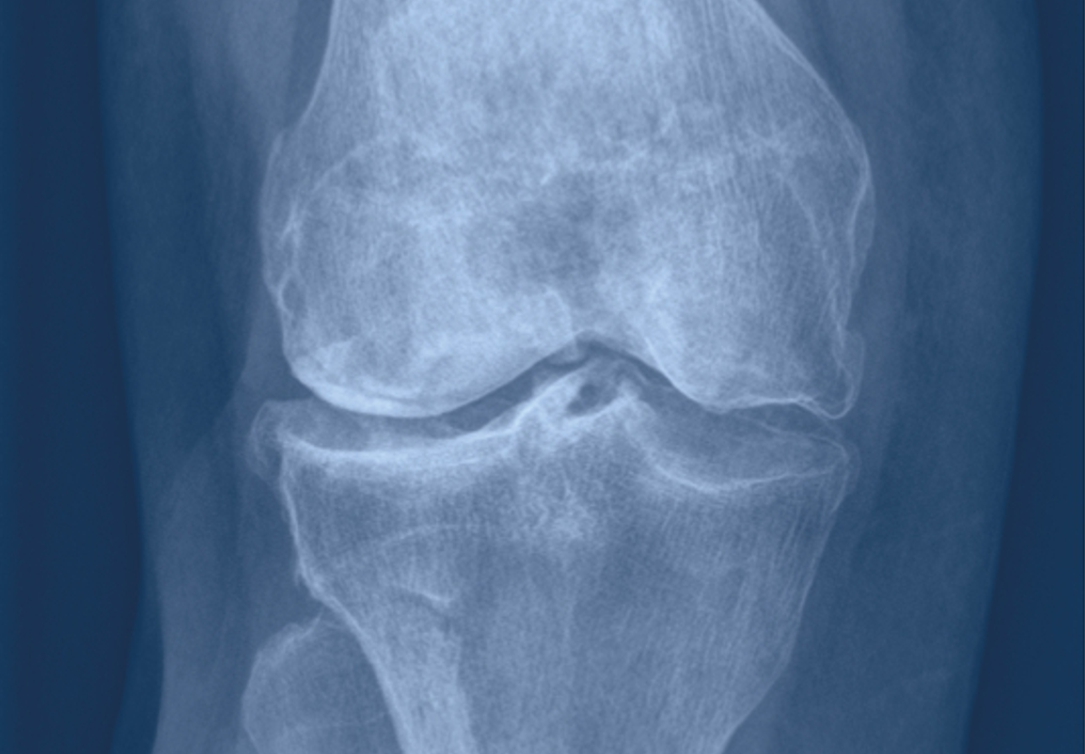

Verschiedene Erkrankungen wie entzündlicher Rheumatismus, Infektionen, Durchblutungsstörungen (Osteonekrose), aber auch Gelenkveränderungen nach Unfällen wie Brüchen oder Band- sowie Meniskusverletzungen, können zu einer Abnützung der Oberfläche des Kniegelenks führen. Man spricht dann von Arthrose. Am häufigsten ist eine solche Arthrose aber altersbedingt und kommt nicht selten familiär gehäuft vor.

Eine Kniearthrose äussert sich in zunehmenden Schmerzen im Knie, die beim Anlaufen, bei Belastung und Aktivität oder sogar im Ruhezustand auftreten können. Es kommt zu einer Einschränkung der Beweglichkeit und als Folge davon zu Hinken. Bei der Behandlung wird zuerst versucht, die Schmerzen durch konservative Massnahmen wie Medikamente («knorpelunterstützende» Mittel, Schmerzmittel) oder Physiotherapie (z. B. mit dem GLA:D-Programm) einzudämmen. Auch die Eigenbluttherapie (PRP-Infiltration ins Kniegelenk) hat sich in den letzten Jahren immer mehr etabliert. Nehmen die Beschwerden trotzdem so zu, dass sie aus Sicht des Patienten seine Lebensqualität in einem nicht mehr akzeptablen Mass einschränken, bleibt nur noch die Möglichkeit, operativ ein künstliches Kniegelenk einzusetzen. Es ist also nicht das auf dem Röntgenbild ersichtliche Ausmass der Arthrose, das über die Durchführung der Operation entscheidet, sondern massgebend ist der Leidensdruck des Patienten.